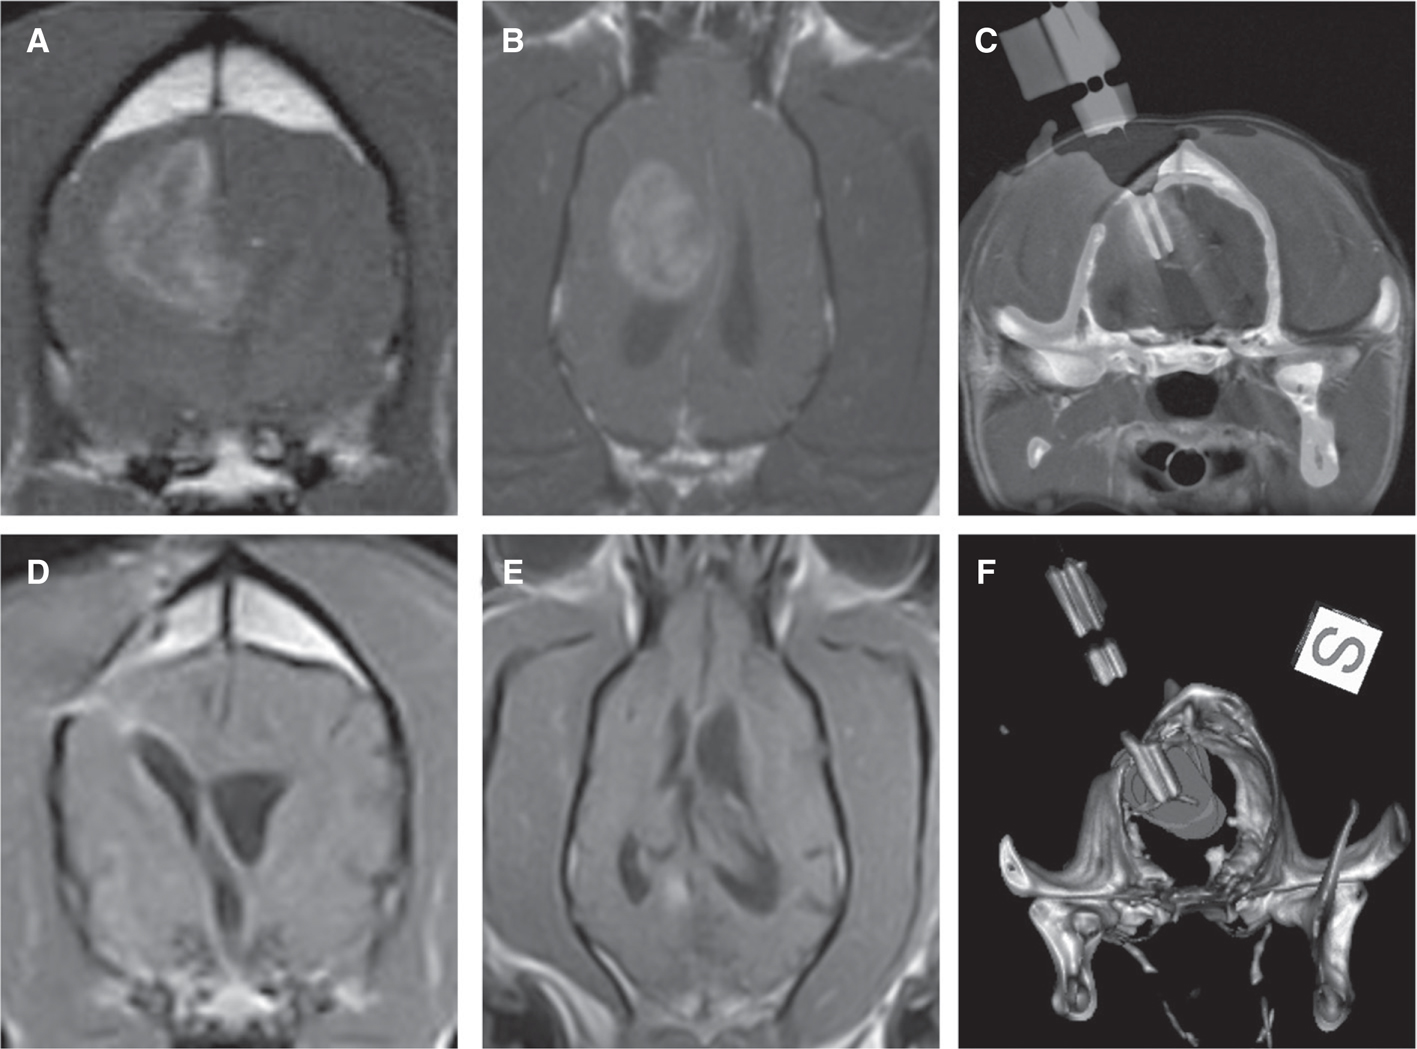

The histopathological and diagnostic imaging features of canine gliomas (Figure 1) are also remarkable similar to their human counterparts (3135). These shared morphologic features facilitate comparative classification and grading of tumors using World Health Organization criteria (36) and performing objective imaging–based therapeutic response assessments using the Response Assessment in Neuro-Oncology (RANO) system criteria (28, 37). However, the frequency of glioma subtypes encountered in dogs differs from that seen in humans (Table 1), with oligodendrogliomas accounting for a significantly higher proportion of all canine gliomas compared to humans (1921, 23, 37).

Fig 1

Figure 1 Comparative morphological and immunophenotypical features of human and canine glioblastoma (GBM). Post-contrast T1-weighted magnetic resonance images from a human (A) and dog (B) demonstrating ring-enhancing cerebral GBM. Classic microscopic features of hypercellularity and pseudopalisading necrosis in a human (C) and canine (E) GBM (H&E stain, bar = 150 μm). GBM from both species demonstrate intense immunoreactvity to IL-13RA2 (D, F).